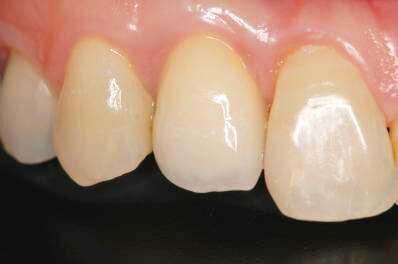

インプラントが骨と結合した後に仮歯を装着します。仮歯では歯の形態や周囲粘膜の状態を整えます。その後、その仮歯を参考にし、色についても相談しながら本歯を作製します。 |